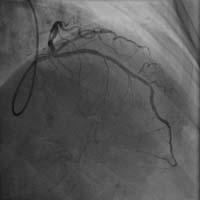

前降支近端严重狭窄 介入术后狭窄消失